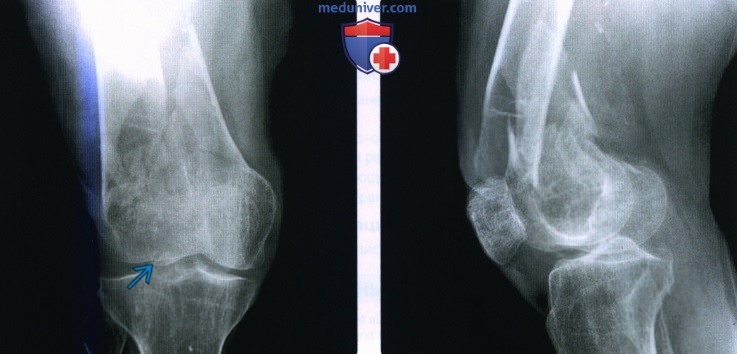

Иллюстрации и снимки, связанные с остеопенией шейки бедра

Раздел: Необычные решения